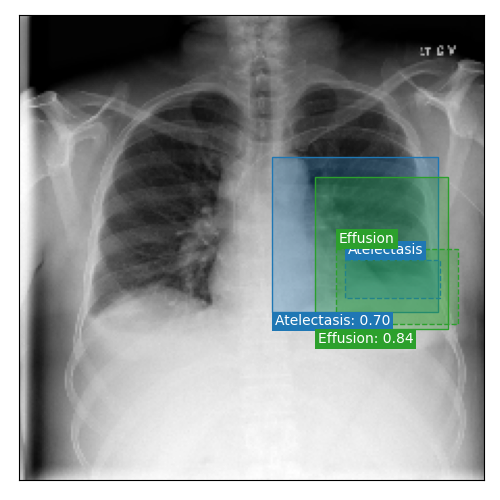

Qualitative Results

As shown in Fig. 4 Loc-ADPD detects cardiomegaly almost perfectly, as it is always exactly localized at one anatomical region. Other pathologies are detected but often with too large or too small boxes as they only cover parts of anatomical regions or stretch over several of them, which cannot be completely corrected using WBF. Detection also works well for predicting several overlapping pathologies. For qualitative comparisons between Loc-ADPD and MIL-ADPD, we refer to Appendix 0.B.